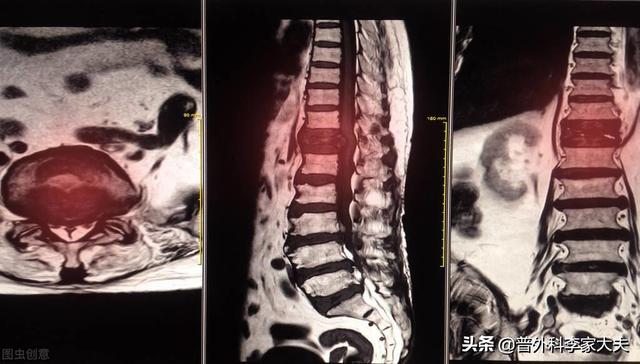

骨転移はどのような痛みに注意すべきですか?骨転移は悪性腫瘍の末期によく見られる症状で、体の他の部位にある原発腫瘍が血液やリンパ液の経路を通って骨に転移し、骨転移を形成することを指します。骨転移は、正常な骨組織が破壊され、腫瘍組織に置き換わっていることを示す。骨転移は病変の特異性により、溶骨型、造骨型、混合型の3つに分類される。骨転移の好発部位は中軸骨(脊椎、骨盤)、肋骨、下部骨幹部で、特に中軸骨が最も多く、これはこの部位の血液供給の特徴と関係しています。下の円のように骨転移が多発し、脊椎の状態が悪い。

骨転移で起こる症状にはどのようなものがありますか?最初の症状は痛みです。骨転移を起こした部位は骨が破壊されるために痛みを感じますが、最初ははっきりした症状がなかったり、断続的な痛みだったりしますが、腫瘍が正常な骨をどんどん破壊して徐々に悪くなっていくため、転移部位の痛みも徐々に悪くなっていきます。臨床的には、体のある部分の骨の痛みで、悪性腫瘍の骨転移という症例に出くわすことがあります。以前、ある症例に出会ったのですが、40歳で、肩が痛く、五十肩かと思い、薬用オイルを数日揉んでも改善が見られず、ますます痛みが強くなったので、病院で検査をしたところ、MRIを撮ったところ、肩甲骨が(腫瘍の)かけらに食べられており、骨転移を考え、胸部CTを撮ったところ、右肺に結節があり、生検をして病理検査をしたところ、肺がんの骨転移でした。その内容は以下の通りである。

骨転移部位では、正常な骨組織が破壊され腫瘍組織に置き換わり、腫瘍細胞は常に増殖しているため、多くの骨転移部位で軟部組織の腫瘤影が見られ、腫瘤が表在する部位であれば触知することができる。また、腫瘍組織による正常な骨組織の侵食は、正常な骨構造の破壊と脆弱化につながるため、正常な外力下でも骨折が生じることがあり、病的骨折と呼ばれます(下図)。脊椎への転移は、疼痛や病的骨折に加えて、脊髄神経根の圧迫を伴い、感覚障害、筋力低下、場合によっては高カルシウム血症などの症状を呈することもあります。

骨転移の磁気共鳴画像法

胸椎に発生した骨転移性癌を示す。